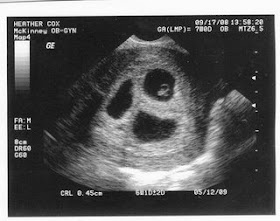

A year ago today...

...our lives changed forever. I remember meeting Bret to go to our first sonogram. As we sat in the waiting room I said a prayer hoping to see the little heartbeat we were told was there. When we found out there were 4 precious heartbeats a train of emotions hit us all at once... shock, thankfulness, excitement, fear, happiness, confusion, hopelessness yet hope all at the same time.